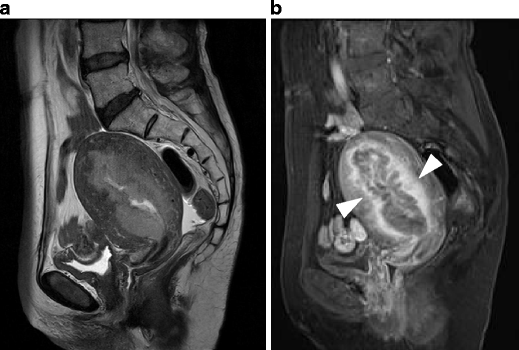

Undifferentiated stromal sarcoma in a 22-year-old female who presented with acute abdomen due to uterine rupture. a Sagittal T2-weighted image demonstrates an ill-defined myometrial mass of heterogeneous appearance in the anterior wall (arrows). The upper portion of the tumor containing fluid-fluid level represents hemorrhagic necrosis within the tumor (arrowheads). b T1-weighted image demonstrates increased signal intensity corresponding to the area of hemorrhagic necrosis (arrowheads). Hemorrhagic ascites of increased signal intensity also is present in the Douglas fossa and uterovesical fossa (asterisks). c Postcontrast T1-weighted image with fat suppression demonstrates heterogeneous enhancement within the solid component of the tumor (arrows)